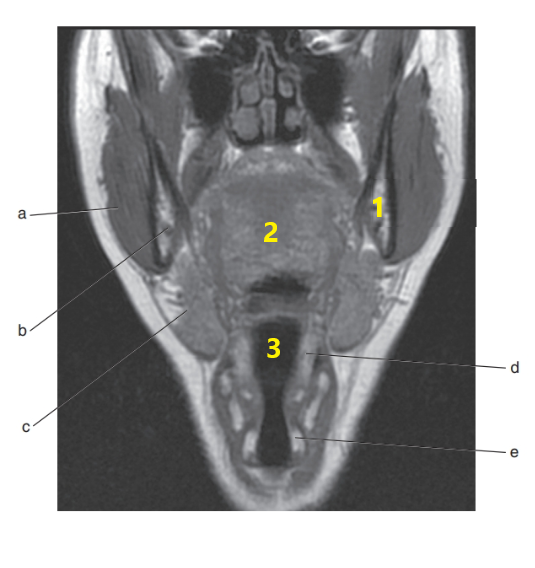

What is # 1 ?

Tongue

What is # 3 ?

Brain stem

Mandible